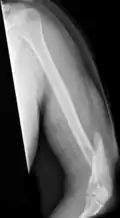

Midshaft humerus fracture with callus formation

Definitive diagnosis of humerus fractures is typically made through radiographic imaging. For proximal fractures, X-rays can be taken from a scapular anteroposterior (AP) view, which takes an image of the front of the shoulder region from an angle, a scapular Y view, which takes an image of the back of the shoulder region from an angle, and an axillar lateral view, which has the patient lie on his or her back, lift the bottom half of the arm up to the side, and have an image taken of the axilla region underneath the shoulder.[9] Fractures of the humerus shaft are usually correctly identified with radiographic images taken from the AP and lateral viewpoints.[12] Damage to the radial nerve from a shaft fracture can be identified by an inability to bend the hand backwards or by decreased sensation in the back of the hand.[5] Images of the distal region are often of poor quality due to the patient being unable to extend the elbow because of pain. If a severe distal fracture is suspected, then a computed tomography (CT) scan can provide greater detail of the fracture. Nondisplaced distal fractures may not be directly visible; they may only be visible due to fat being displaced because of internal bleeding in the elbow.[7]